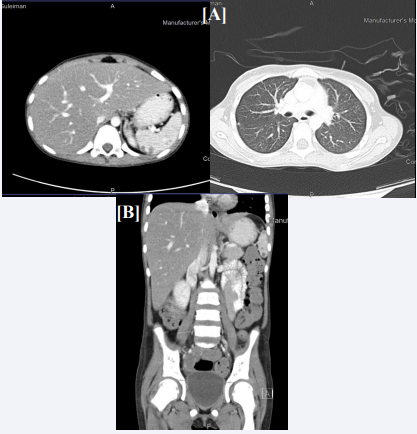

A 9 years old girl with newly diagnosed Acute Lymphoblastic Leukemia (B-ALL). She had pallor, petechiae and ecchymosis as presenting complaints. On examination, there was pallor, scattered petechiae, mild hepatomegaly, palpable spleen tip without significant lymphadenopathy. Investigations were done and the WBC count was 12.6, the Hb was 6.5 and the platelets count was 94. Bone Marrow examination showed an overall immunophenotype results that are most consistent with B lymphoblastic leukemic cells in common BALL. CT chest showed new tiny pulmonary nodules are noticed one in the left lower lung anterior measures about 3 mm the other tiny nodule in the right mid lung lobe anterior subpleural location measures about 3.5 mm while abdominal CT showed Both kidneys show bilateral scattered focal hypodensities/esons the largest seen in the left kidney measuring about 6.1 X 3.9 mm Partial opacification of the proximal small bowel lope with oral contrast with evidence of focal soft tissue density seen in the proximal jejunum could be related to intussusception however other underlying pathology cannot be ruled out, Evidence of mild intra-abdominal free fluid mainly in pelvis. The large bowel it loaded with fecal matter [Figure 3]. Follow up with cytogenetic study for further classification and diagnosis was advised. The diagnosis was a case of acute Lymphoblastic Leukemia for standard risk chemotherapy protocol. It was recommended to continue to follow up with pediatric oncology and bactrim prophylaxis together with Chlorehexidine Mouth Wash was advised.

Figure 3 (A) Chest CT scan chest showing tiny pulmonary nodules are noticed one in the left lower lung. (B) Abdominal CT with contrast showing numerous nodules in the liver, spleen and kidneys.